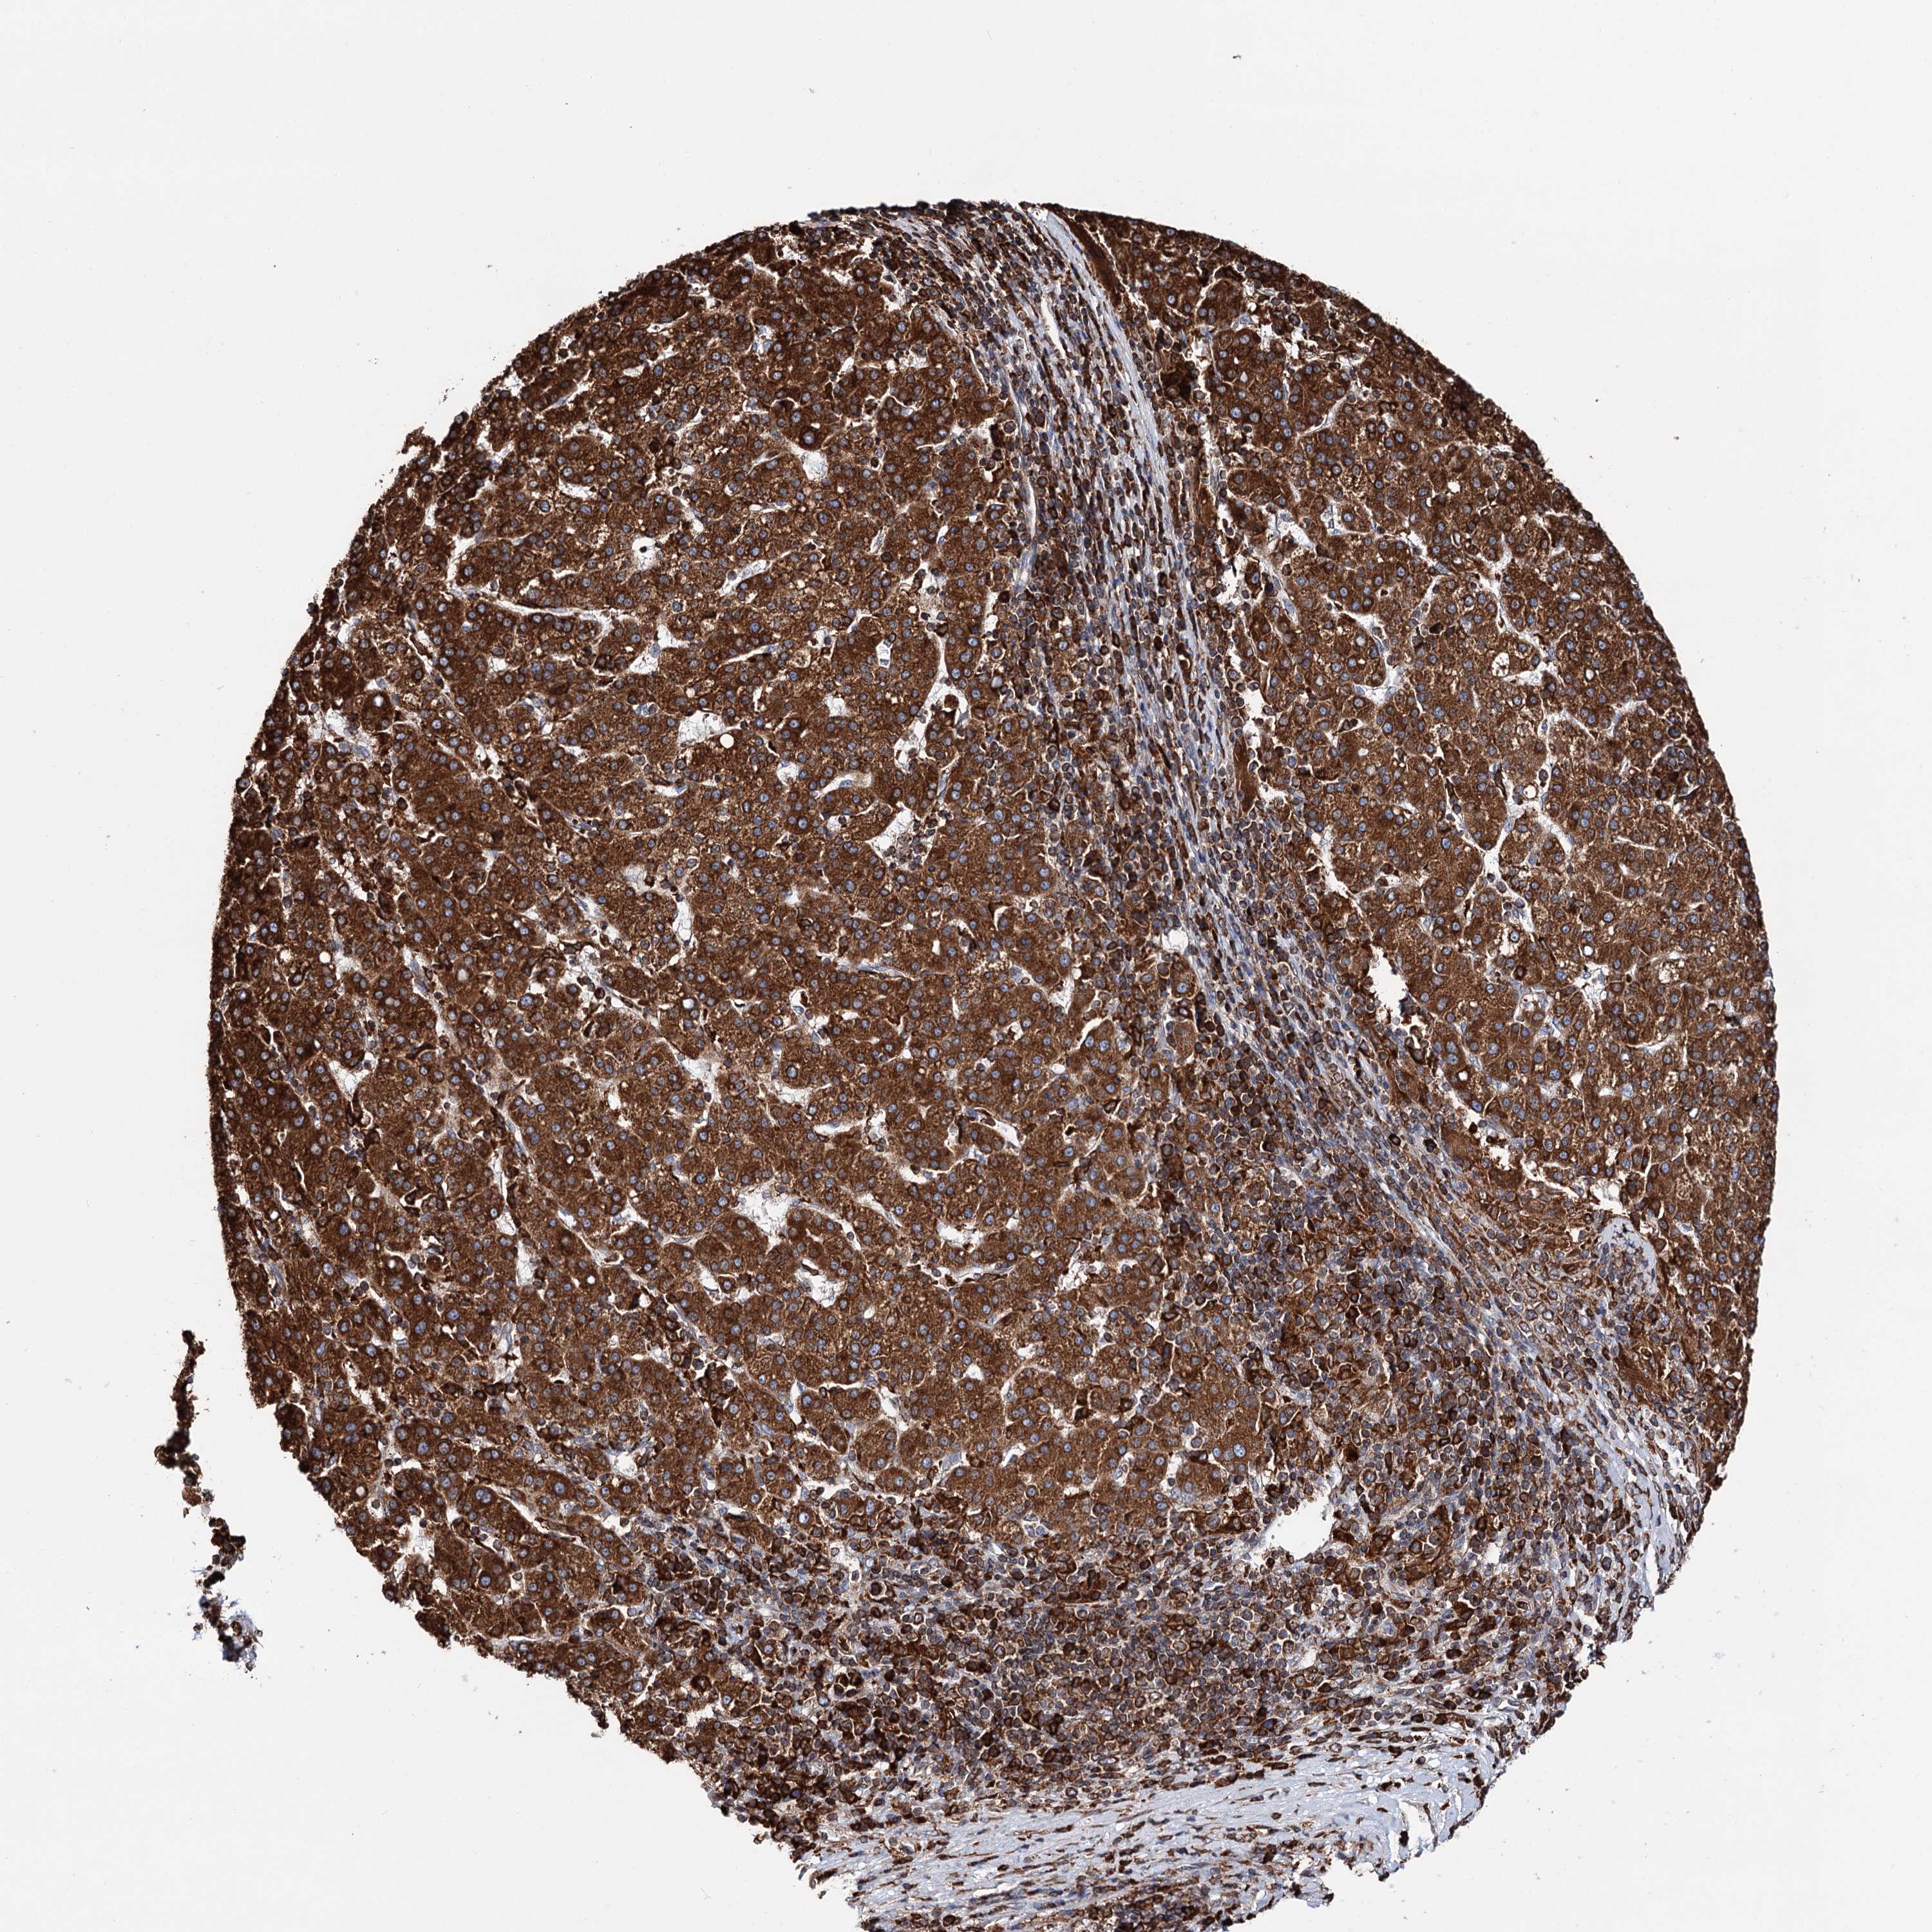

LIVER CANCER - Protein expressioni

A mouse-over function shows sample information and annotation data. Click on an image to view it in a full screen mode. Samples can be filtered based on level of antibody staining by selecting one or several of the following categories: high, medium, low and not detected. The assay and annotation is described here.

Note that samples used for immunohistochemistry by the Human Protein Atlas do not correspond to samples in the TCGA dataset.

Antibody stainingi

Antibody staining in the annotated cell types in the current human tissue is reported as not detected, low, medium, or high, based on conventional immunohistochemistry profiling in selected tissues. This score is based on the combination of the staining intensity and fraction of stained cells.

Each image is clickable and will lead to virtual microscopy that enables deeper exploration of all samples and also displays staining intensity scores, fraction scores and subcellular localization as well as patient and tissue information for each sample.

Antibody HPA039363

Antibody HPA039456

Staining

High

Medium

Low

Not detected

Intensity

Strong

Moderate

Weak

Negative

Quantity

>75%

75%-25%

<25%

None

Location

Nuclear

Cytoplasmic/membranous

Cytoplasmic/membranous,nuclear

Cholangiocarcinoma

Carcinoma, Hepatocellular, NOS